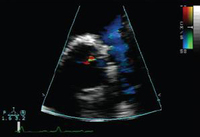

Ecocardiografia com Doppler em um paciente com regurgitação pulmonar após reparo de tetralogia de Fallot, revelando via de saída do ventrículo direito não obstruída. O paciente tem ventrículo direito não restritivo

De: Chaturvedi RR, Redington AN. Heart. 2007 Jul;93(7):880-9; usado com permissão